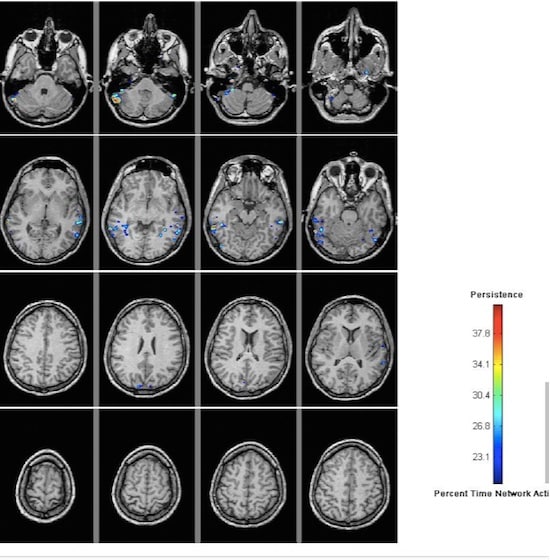

Brain Imaging

The study involved brain imaging of these 42 volunteers with a method called structural magnetic resonance using the magnetic resonance imaging instruments at NBRC, India.

The study enabled them to find out the shape and size of different regions of the brains of these individuals.

“What we discovered from the structural MRI scanning was remarkable.

Numerous regions in the brains of the pandits were dramatically larger than those of controls, with over 10 percent more grey matter across both cerebral hemispheres, and substantial increases in cortical thickness.

“Although the exact cellular underpinnings of grey matter and cortical thickness measures are still under investigation, increases in these metrics consistently correlate with enhanced cognitive function.” Dr. James Hartzell